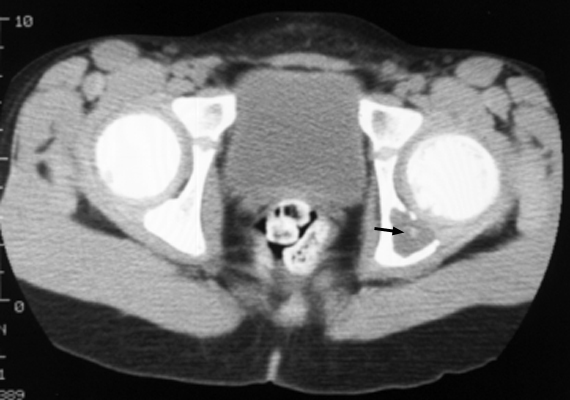

Single slice of a CT scan of the pelvis with an abnormal lucent area with a sclerotic focus within it in the left hemipelvis. This sign was originally utilized to describe an unusual radiographic manifestation of Eosinophilic Granuloma. It is a round, lucent defect with a bony density, or sequestrum, in its center. This is not pathognomonic as other disease entities such as osteomyelitis can have a similar appearance.

CT acetabulum - Click on the image for a larger version